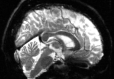

3.7 Comparison of PyHySCO with HySCO and TOPUP

Table 6 reports the runtime and correction quality for PyHySCO using GN-PCG, HySCO, and TOPUP. On real 3T and 7T data, PyHySCO achieves lower loss and higher relative improvement between corrected images than HySCO, and higher relative improvement than TOPUP. The runtime on CPU for real data is 1-2 minutes for HySCO and over 1 hour for TOPUP, while PyHySCO on GPU has runtimes of 10-13 seconds. For the simulated dataset, PyHySCO requires an average of 1 minute on GPU, HySCO an average of 12.6 minutes on CPU, and TOPUP an average of 8.5 hours on CPU. Using the ground truth field maps from the simulated dataset, PyHySCO achieves the lowest average field map relative error, 14.48%, compared to 19.70% for HySCO and 16.36% for TOPUP. Figures 7, 8, and 9 show the field map and corrected images for one example subject from each dataset. The results of the methods are similar, and the resulting field maps are comparable to those of the existing tools, HySCO and TOPUP, while PyHySCO is considerably faster.